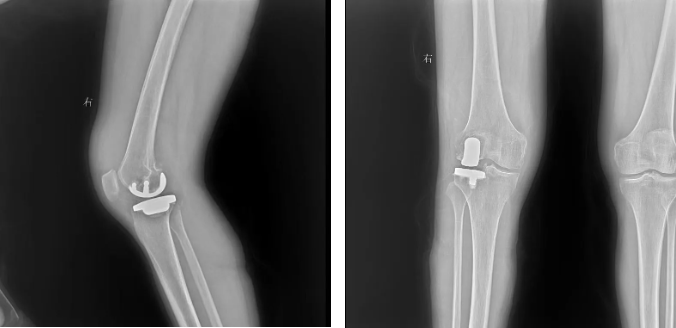

因关节炎反复发作多年,今年3月,长沙的李女士在医院接受了右膝关节置换术。术后,因为惧怕疼痛,她一直卧床静养,很少活动。结果一段时间后,她发现自己越躺右膝反而越痛,右腿变得弯曲、伸直不能,只能在他人的搀扶下拄拐短距离行走。不仅如此,因术后活动减少导致下肢静脉血液回流不畅,她的右下肢还形成了血栓。